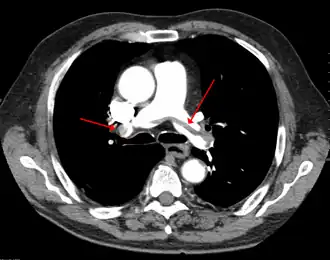

| Tomografia computadorizada de tórax com agente de radiocontraste mostrando múltiplos defeitos de enchimento dos principais ramos das artérias pulmonares, devido a embolismo pulmonar crônico e agudo. | |